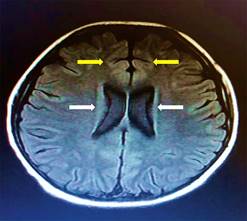

La biometría hemática con leucocitos de 18.75 × 1010/L, con neutrófilos de 82%. Los reactantes de fase aguda sin alteraciones. En el LCR se evidenció pleocitosis y positividad de anticuerpos inmunoglobulina G (IgG) para citomegalovirus y rubéola. Los hemocultivos periféricos y el cultivo de LCR sin crecimiento. Las imágenes de tomografía computarizada de cráneo (TAC) no mostró alteraciones. La resonancia magnética (RM) T2-FLAIR evidenció hiperintensidad en zonas paraventricular y en la corteza frontal (Figura 1).

Figura 1: Resonancia magnética cerebral T2-FLAIR. Se muestra hiperintensidad en T2-FLAIR de ganglios basales (flechas blancas) y corteza frontal (flechas amarillas).

Por otro lado, de acuerdo con Zhao y colegas, un resultado anormal en la RM podría asociarse a un peor pronóstico.1,4 En 50% de los casos se pueden encontrar hiperintensidad en la corteza frontal y en lóbulo temporal medial, además de la corteza cerebelosa, médula espinal y bulbo raquídeo.4,22,23